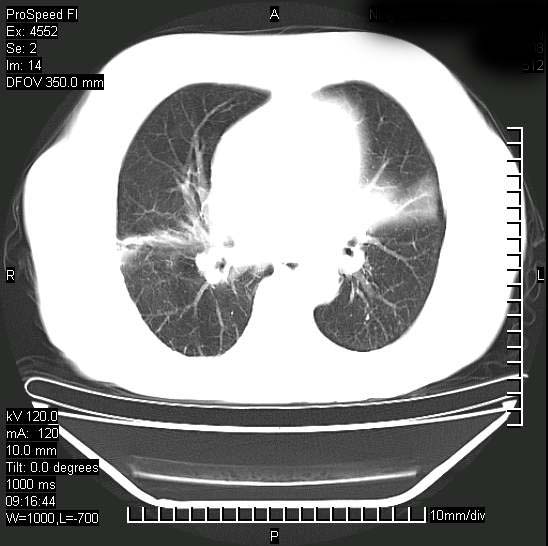

十几年前曾患肺结核,一周前突咳血约100ml,中性粒细胞稍高,诊断两上肺陈旧结核,下肺炎症,给予抗炎治疗,近几日晚上高热,39度,仍咳少量血,4天前ct及今天ct上传。

[face=黑体]8月30日[/face]

今天ct

短短几天内,病变范围明显增多扩大,以左侧明显,而且双侧出现胸水,还是考虑感染.

短短几天内,病变范围明显增多扩大,以左侧明显,而且双侧出现胸水,我更多考虑左侧中心性肺癌并并阻塞性不张及肺炎,炎症变化也太快了!

无论是肿瘤还是炎症4天的时间都发展够快的,并且还在治疗中,如果说是左肺癌那么右肺的病变不好解释,本人更加倾向于炎症,左肺舌叶支气管被痰栓或血凝块堵塞,造成阻塞性肺炎。

1)两肺结核并感染。2)不排除左肺上叶中央型肺癌并阻塞性肺炎、肺不张可能;建议行纤支镜检查。3)右肺门及纵隔淋巴结肿大。4)双侧胸腔积液。